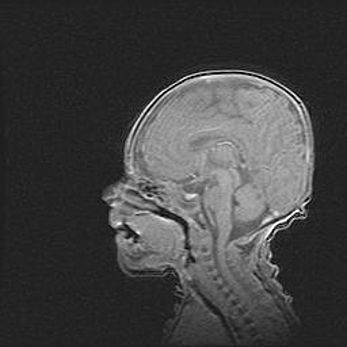

Открытая гидроцефалия.

Возраст: 9 месяцев 12 дней

Вес: 6800 г

Пол: мужской

Окружность головы: 41,5 см

Срок гестации: 28 недель

Гидроцефалия головного мозга у новорожденных имеет характерный признак: опережающий рост окружности головы приводит к визуально хорошо определяемой гидроцефальной форме сильно увеличенного в объёме черепа. Детские неврологи определяют следующие симптомы гидроцефалии у грудничков: выбухающий напряжённый родничок, частое запрокидывание головы, смещение глазных яблок к низу.